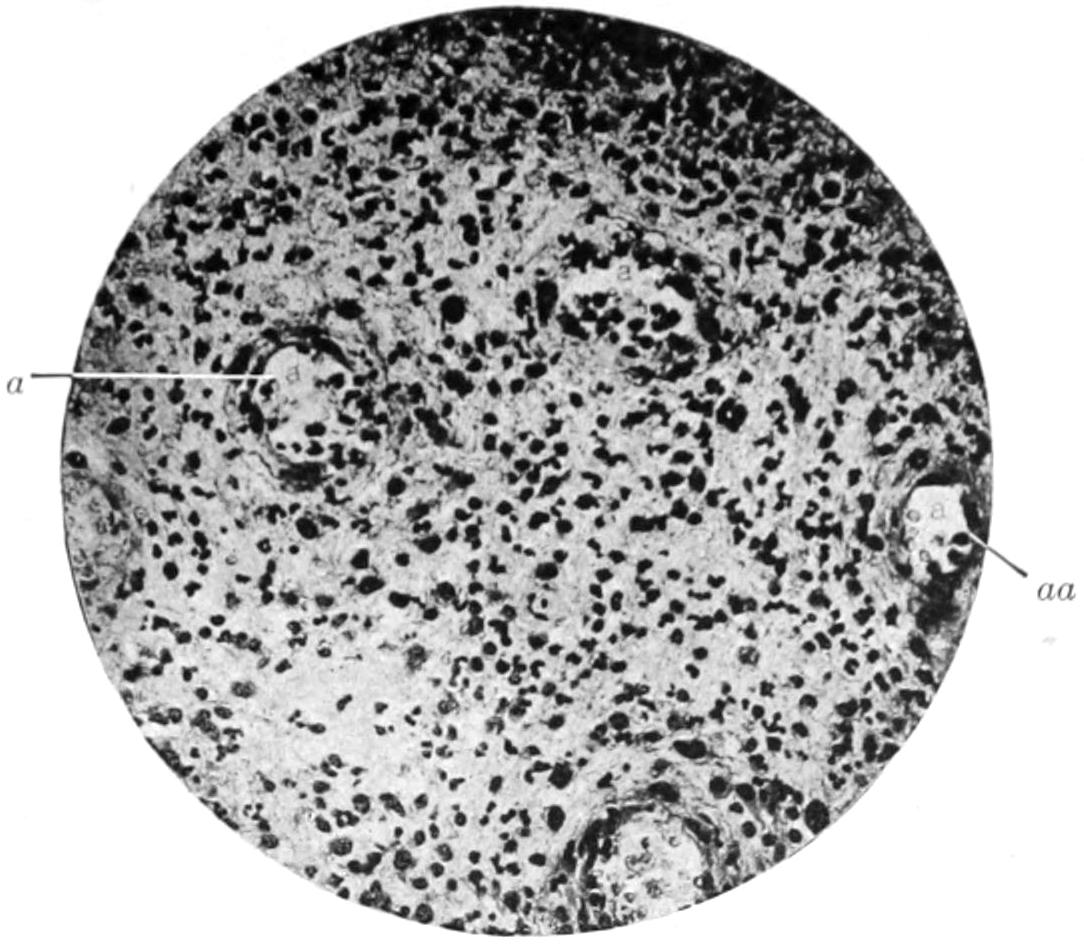

PLATE I

PLATE I.

BLOOD.

(Ehrlich triple stain.)

Fig. I. TYPES OF LEUCOCYTES.

a. Polymorphonuclear Neutrophile. b. Polymorphonuclear Eosinophile. c. Myelocyte (Neutrophilic). d. Eosinophilic Myelocyte. e. Large Lymphocyte (large Mononuclear). f. Small Lymphocyte (small Mononuclear).

Fig. II. NORMAL BLOOD.

Field contains one neutrophile. Reds are normal.

Fig. III. ANÆMIA, POST-OPERATIVE (secondary).

The reds are fewer than normal, and are deficient in hæmoglobin and somewhat irregular in form. One normoblast is seen in the field, and two neutrophiles and one small lymphocyte, showing a marked post-hæmorrhagic anæmia, with leucocytosis.

Fig. IV. LEUCOCYTOSIS, INFLAMMATORY.

The reds are normal. A marked leucocytosis is shown, with five neutrophiles and one small lymphocyte. This illustration may also serve the purpose of showing the leucocytosis of malignant tumor.

Fig. V. TRICHINOSIS.

A marked leucocytosis is shown, consisting of an eosinophilia.

Fig. VI. LYMPHATIC LEUKÆMIA.

Slight anæmia. A large relative and absolute increase of the lymphocytes (chiefly the small lymphocytes) is shown.

Fig. VII. SPLENO-MYELOGENOUS LEUKÆMIA.

The reds show a secondary anæmia. Two normoblasts are shown. The leucocytosis is massive. Twenty leucocytes are shown, consisting of nine neutrophiles, seven myelocytes, two small lymphocytes, one eosinophile (polymorphonuclear) and one eosinophilic myelocyte. Note the polymorphous condition of the leucocytes, i. e., their variations from the typical in size and form.

Fig. VIII. VARIETIES OF RED CORPUSCLES.

a. Normal Red Corpuscle (normocyte). b, c. Anæmic Red Corpuscles. d-g. Poikilocytes. h. Microcyte. i. Megalocyte. j-n. Nucleated Red Corpuscles. j, k. Normoblasts. l. Microblast. m, n. Megaloblasts.

The value of a careful blood examination is well illustrated by Plate I, prepared by Dr. Irving P. Lyon, in which are displayed the alterations of greatest interest to the surgeon.